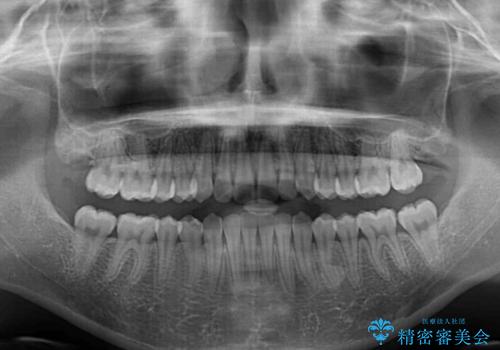

- 口元のデコボコを気にして来院された患者様です。

前歯の捻れにより口元が閉じにくくなっていたため、歯列全体の側方への拡大と、歯と歯の間を少し削ってスペースを獲得することとしました。

ゴムかけをしっかりと行ってもらい、スッキリとした口元に仕上げることができました。